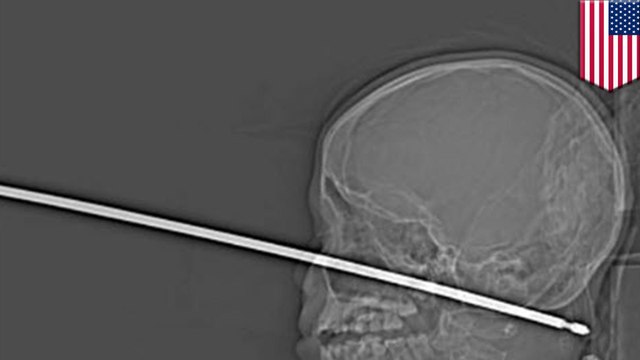

Man impaled on lamppost after falling 50 ft from building, survives

Check out our official website: us.tomonews.net/ Check out our Android app: goo.gl/PtT6VD Check out our iOS app: bit.ly/1gO3z1f ­ ­ A man from China's Sichuan province, Li Jen, amazingly survived being impaled on a lamppost after falling 50-feet from building. Li returned home one day to discover that he had locked himself out. Instead of paying for a locksmith to help him open the door, he decided to go back outside and scale a 50-foot high wall to reach his apartment balcony. During his climb, Li slipped and fell directly onto a lamppost, impaling himself on the nine-centimeter-wide pole. He ended up dangling midair several feet from the ground. People nearby heard Li screaming in agony and called emergency services. Fireman were forced to cut the lamppost and transport it, with Li still attached to it, to the hospital. Medics said the pole luckily managed to miss all of Li's essential organs after it speared into his body. It took a three-hour surgery before doctors were able to remove the pole from Li's body. He was placed in intensive care, and is expected to make a full recovery. ­ ­ Welcome to TomoNews, where we animate the most entertaining news on the internets. Come here for an animated look at viral headlines, US news, celebrity gossip, salacious scandals, dumb criminals and much more! Subscribe now for daily news animations that will knock your socks off. Check out our Android app: play.google.com/store/apps/details?id=com.nextmedia.gan Check out our iOS app: itunes.apple.com/app/tomonews/id633875353 For news that's fun and never boring, visit our channel: youtube.com/user/TomoNewsUS Subscribe to stay updated on all the top stories: youtube.com/channel/UCt-WqkTyKK1_70U4bb4k4lQ?sub_confirmation=1